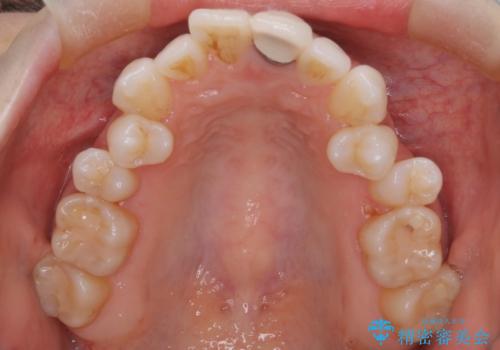

- 患者様は、歯並びの乱れ(叢生)を整えたいが、前歯の突出感は気にならないとのことで来院されました。診察の結果、全体的な歯列のスペース不足により抜歯が必要と判断。しかし、前歯を大きく下げる必要はなかったため、小臼歯の中でも5番(第二小臼歯)を抜歯する治療計画を立てました。装置は、上顎が舌側(リンガル)、下顎が表側(審美ワイヤー)のハーフリンガル矯正を採用し、目立ちにくさと効率的な歯の移動を両立しました。

抜歯によって歯を並べるためのスペースを確保。その後、ハーフリンガル矯正を用いて、上顎は舌側から、下顎は目立ちにくいワイヤーで歯を誘導し、歯列全体を整えました。治療期間を通じて、噛み合わせのバランスも改善し、機能的にも審美的にも理想的な仕上がりとなりました。患者様からは「目立たずに矯正でき、きれいな歯並びになって嬉しい」とご満足いただきました。